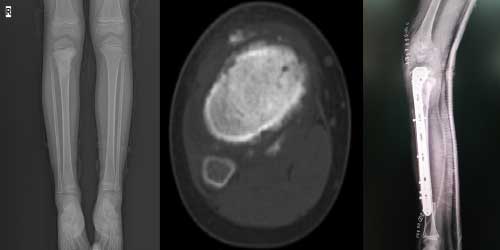

Omurga metastazı, kanserin ilk olarak iç organlarda gelişip daha sonra omurga kemiklerine yayılması sonucu oluşan bir durumdur. Çoğunlukla kan yoluyla sıçrayan bu tür metastaz, hastalarda sırt ve bel ağrısı gibi şikayetlerle kendini gösterir. Erken teşhis ve uygun tedavi yöntemleri, hastaların yaşam kalitesini artırmada kritik bir rol oynar.

Tedavide başarıyı artıran en önemli etkenlerden biri ameliyat öncesi iyi bir hazırlık ve cerrahi planlama yapmaktır. Her şeyden önce tanı doğru konmalı. Bunun için hasta iyi dinlenip, detaylı muayene edildikten sonra tetkikleri dikkatli incelenmelidir.